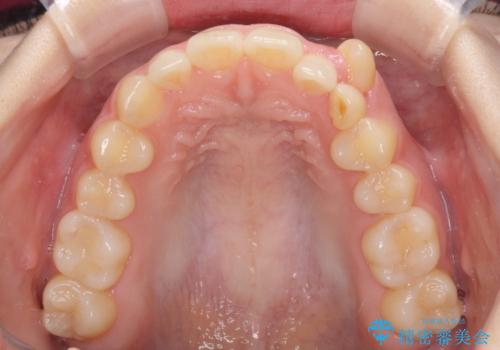

- 八重歯を気にして来院された患者様です。

八重歯のために乳歯が残存していたため、乳歯を抜去して八重歯となっている犬歯を歯列に収めることとしました。

八重歯の移動量が多くなるため、インビザラインと併用してワイヤー矯正を行い、八重歯を改善した後に、上下歯列をインビザラインで整えることとしました。

犬歯は歯根が長くて太いため移動に時間がかかる上に、周囲の歯が八重歯に寄ってきてしまうため、仕上がるまでに期間がかかりました。